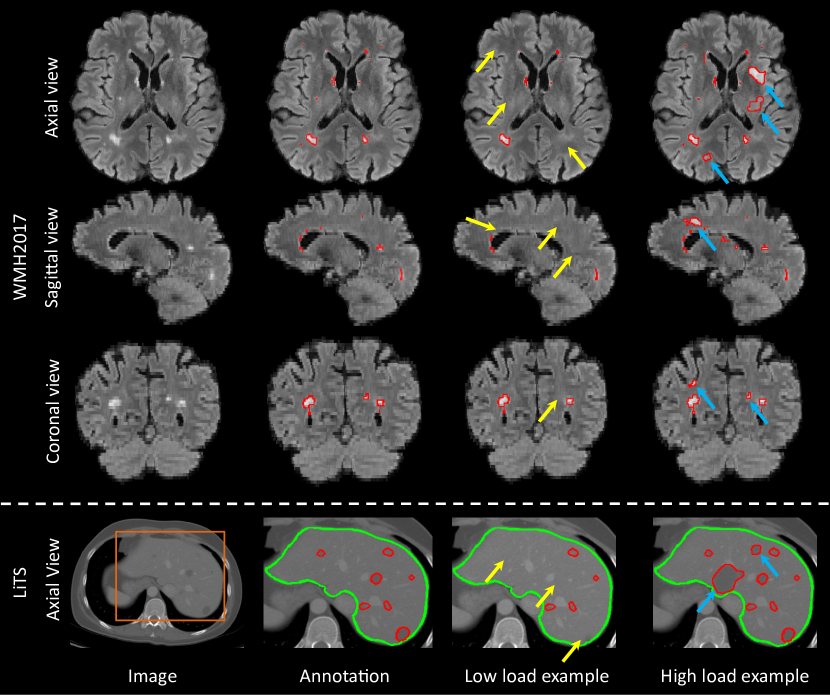

For each image to be augmented, we sample the target lesion load, vtarsubscriptvtar\mathrm{v_{tar}}, from the distribution and apply lesion populating or inpainting iteratively to achieve this target. If vtarsubscriptvtar\mathrm{v_{tar}} is lower than vcursubscriptvcur\mathrm{v_{cur}}, lesion inpainting is applied; if vtarsubscriptvtar\mathrm{v_{tar}} is greater than vcursubscriptvcur\mathrm{v_{cur}}, lesion populating is applied. We present examples of inpainting and populating as examples of LesionMix in low load and high load distribution setting examples, respectively, in Figure 3. We present the algorithm of LesionMix in Algorithm 1.

Refer to caption

Figure 3: Original image, annotation and augmented data by LesionMix with low and high load image examples for both brain (first three rows) and liver (fourth row) datasets. Red denotes brain or liver lesions. Green denotes the liver. Low load example demonstrates performance of inpainted lesions, indicated by yellow arrows. High load example shows populated lesions, indicated by blue arrows.